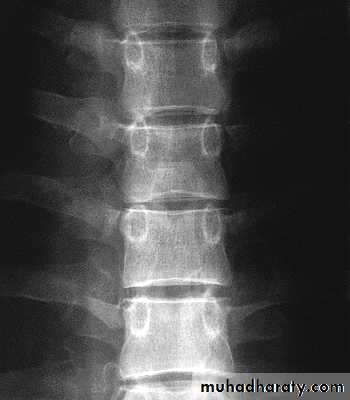

Lumbar Spine X Ray

Lateral radiograph

A/P radiograph• Sacrum

Curvature is Lordotic

Facets are aligned vertically and allow bending

Vertebral body is kidney shaped in MRI